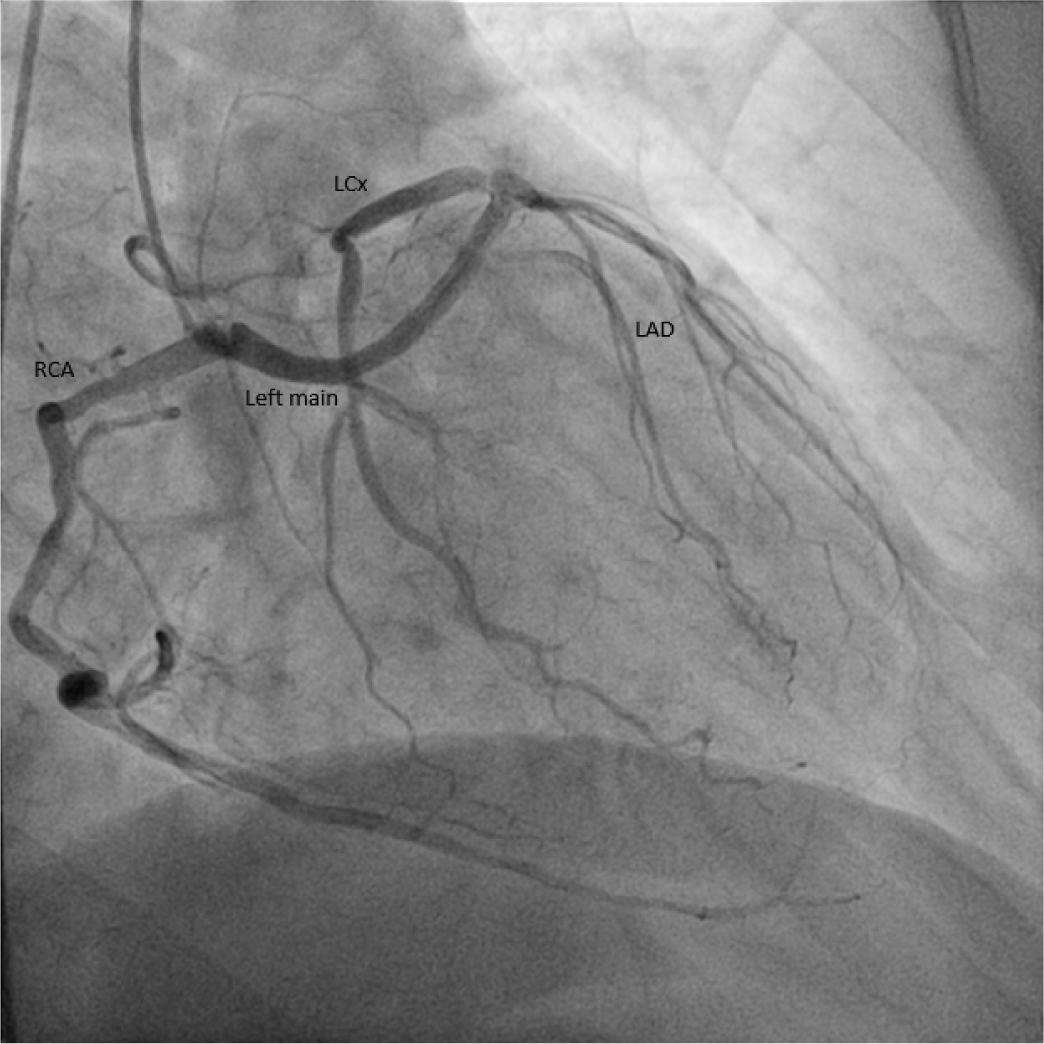

Twenty-nine percent of the patients had significant coronary artery disease (figure 2). Most of the patients had no coronary lesions (58%). The most common coronary artery anomalies were the anomalous origin of left circumflex artery from the right coronary artery (38.71%) (figure 3) and the anomalous origin of right coronary artery from right coronary sinus of Valsalva (19.35%) (table 2) and the least common was anomalous origin of RCA from the LAD (0.017%) (figure 5). Eight (25.8%) patients underwent coronary revascularization by percutaneous coronary intervention (7 patients − 22.58%) or coronary artery bypass grafting (1 patient − 3.22%). No death or significant complication were recorded in the 31 patients during the 5 years follow-up.

Anomalous origin of left circumflex artery from the right coronary artery.